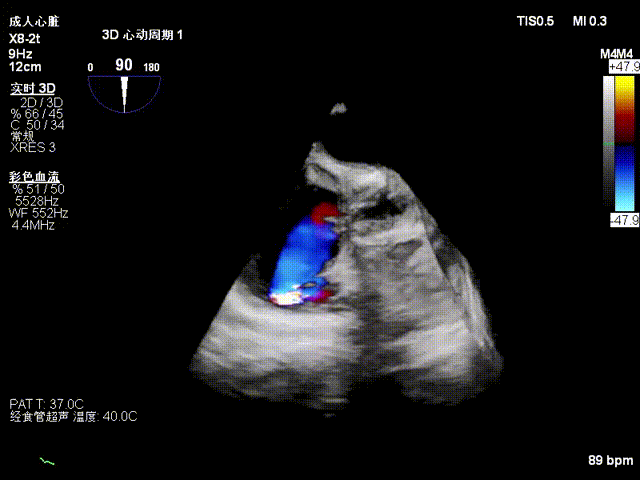

Echocardiographic Findings:Severe tricuspid regurgitation (4+; average vena contracta width, 12 mm). The regurgitation was predominantly anteroseptal and central, with a small posteroseptal component. During systole, the anterior and septal leaflets protruded slightly into the right atrium, with a protrusion height of 2.6 mm. A 6 mm gap was observed at the anteroseptal and central regions. Tricuspid annular dilatation was present (mean annular diameter, 40 mm), with a prominent gap at the anteroseptal region.

Preoperative 3D view of regurgitation